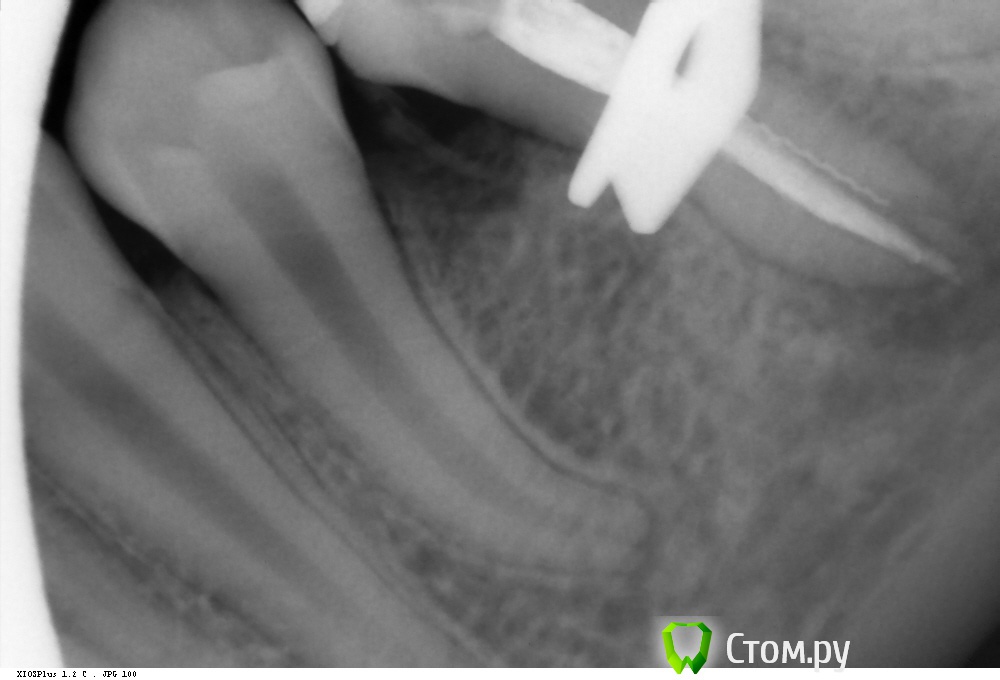

Shaid Опубликовано 9 марта, 2014 Поделиться Опубликовано 9 марта, 2014 (изменено) Пациентка, 14 лет обратилась с постоянной ноющей болью в 35 зубе, болями при накусывании.Объективно: пломба на жевательной и дистально-контактной пов-ти. В канале гуттаперча. Перкуссия +.Распломбировал гутту(оставил часть в апексе, потому что не смог вытащить, а время приема заканчивалось), промыл(кровило), оставил кальций.Какова дальнейшая тактика в данном случае?Стоит ли ждать формирования апекса(вести через кальций) или на следующее посещение закрыть мта? Нужна ли РВК? Кому в апексе видится латераль? Изменено 9 марта, 2014 пользователем Shaid Ссылка на комментарий

Kolchanov Опубликовано 9 марта, 2014 Поделиться Опубликовано 9 марта, 2014 14 лет обратилась с постоянной ноющей болью в 35 зубе Когда зуб был лечен впервые? больше похожу на глубокий сплит.. Думаю, что все проще. Зуб помер или ему помогли помереть в стадии незакрытой верхушки. И сформироваться ей уже не дано. Это довольно сложный зуб и я бы донес до родителей информацию об этом. Если будут готовы, то послать, но послать желательно адресно к тому, кто сможет это сделать. Только в случае отказа (желательно письменно это дело закрепить, что мол зуб сложный и т.д.) браться самому. После полного удаления гуттаперчи есть снимок? 1 Ссылка на комментарий

Shaid Опубликовано 10 марта, 2014 Автор Поделиться Опубликовано 10 марта, 2014 Это довольно сложный зуб и я бы донес до родителей информацию об этом.Донес. но послать желательно адресно к тому, кто сможет это сделать.Имеете ввиду микроскописта? После полного удаления гуттаперчи есть снимок?Полного удаления гуттаперчи не было) в апексе осталось. Есть только такой снимок(с кальцием), хотя ничего информативного, на мой взгляд, он не несет. Ссылка на комментарий

Kolchanov Опубликовано 10 марта, 2014 Поделиться Опубликовано 10 марта, 2014 Клади не контрастный гидроксид, если хочешь посмотреть сколько старого материала осталось. Кальсепт, например.Даже когда на рентгенограмме все пучком, заглянешь с оптикой в канал и удивишься, сколько там еще осталось по стенкам. Микроскоп бы хорошо. Не будешь же гуттаперчу в апексе в Триоксидент вмуровывать.Какой там размерчик получился? По снимку кажется, что и 140 пролетит. 1 Ссылка на комментарий